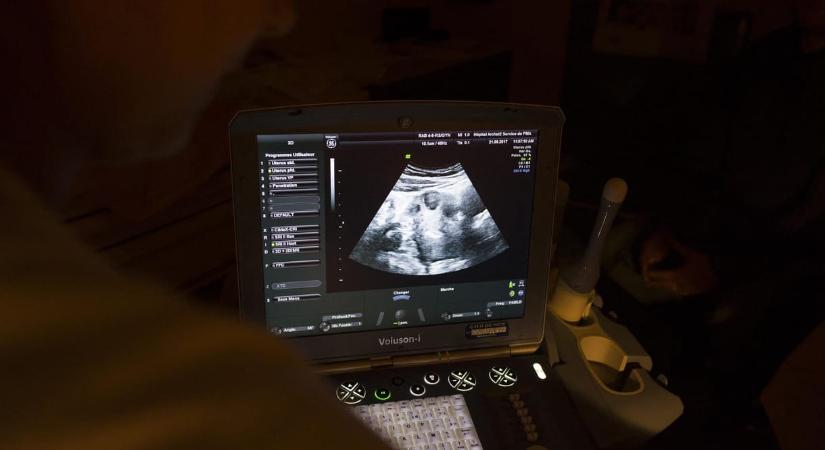

Kipróbálták magzatoknál az őssejtterápiát, ami ezután történt, az rengeteg ember életét megváltoztathatja

Biztonságosnak bizonyult a nyitott gerinc problémájára kidolgozott eljárás az első vizsgálatok alapján. A magzati beavatkozás sok gyermek életét teheti könnyebbé a jövőben.